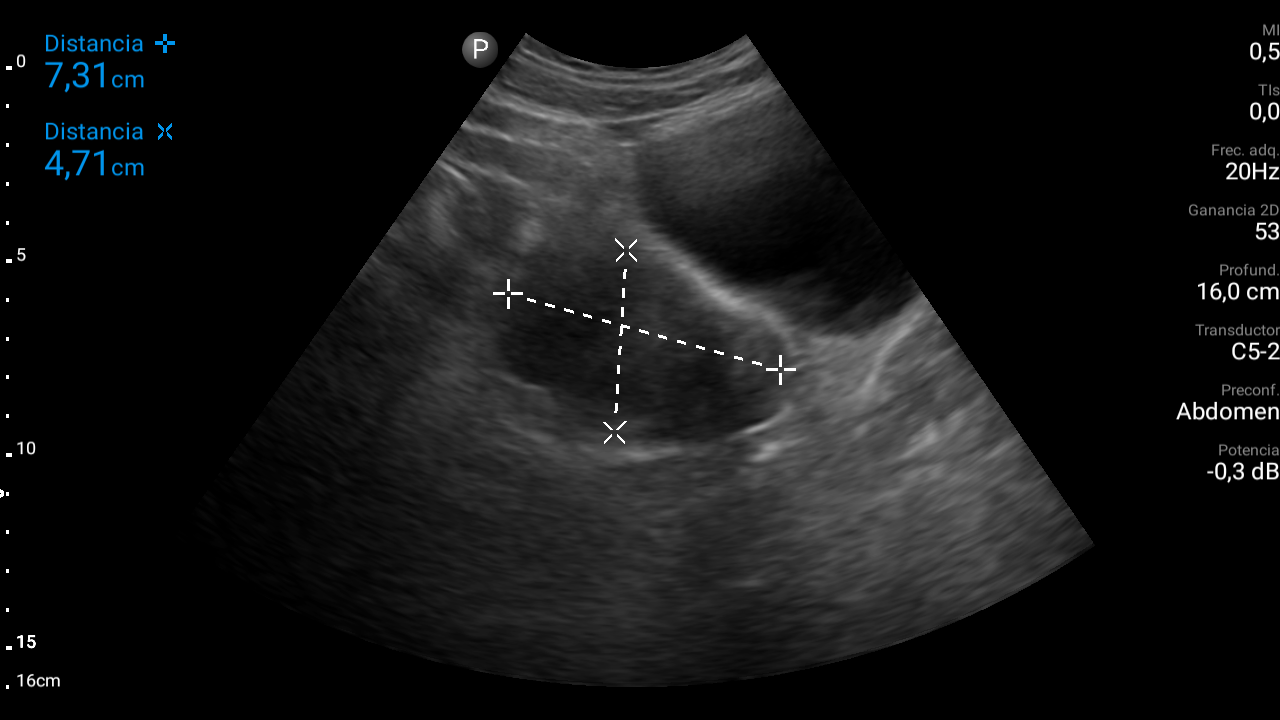

Ecografía abdominal: se observa masa hipoecoica dependiente de útero por lo que se remite de forma preferente a ginecología.

• Ecografía transvaginal: masa uterina compatible con mioma uterino.

Diagnóstico: mioma uterino.